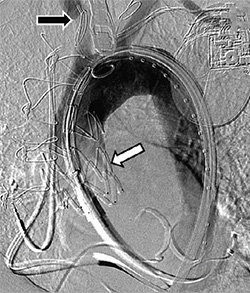

Fluoroscopic imaging of proximal (white arrow) aortic endograft following deployment with visible cerebral protection system (black arrow)

The NewYork-Presbyterian/Columbia University Aortic Center aggressively offers endovascular and minimally invasive therapy for a variety of aortic diseases utilizing cutting-edge technologies. Thoracic endovascular aortic repair (TEVAR) of the ascending aorta and aortic arch, which is currently reserved for patients unable to undergo surgical repair, is associated with increased risk of stroke. With promising data related to use of the Sentinel Cerebral Protection System in TAVR and TEVAR of the descending aorta, cardiothoracic and vascular surgeons with the Aortic Center presented the first published report of the cerebral protection device during TEVAR for an ascending aortic aneurysm in the September 29, 2018, issue of Seminars in Thoracic and Cardiovascular Surgery.

The 85-year-old female patient was referred for evaluation of a chronic ascending aortic aneurysm. Preoperative computed tomography angiography revealed an increasingly dilated ascending aorta. Given the patient’s age, prior cardiac surgical history, medical comorbidities, and elevated risk of perioperative stroke, the patient was offered endovascular repair with utilization of the cerebral protection. The cerebral protection system was removed without incident with no embolic debris noted within the system’s filters following retrieval. The patient was discharged the following day without any evidence of neurologic deficit.